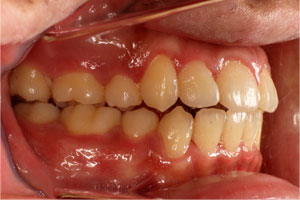

こちらの初診(男性)の患者さんは、開咬合 / 叢生歯列の症状がありました。

1期治療 8歳9ヶ月 2期治療 12歳4ヶ月から治療を開始し、1期治療 7ヶ月 2期治療 2年5ヶ月の間、スタンダードエッジワイズ法(与五沢エッジワイズシステム)を用い矯正治療を行いました。

| 症例分類 | 開咬合 / 叢生歯列 / 偏位咬合 | |||||||||||||||||||||||||||||||||||||||||||||||||||||||||||

| 動的治療期間 | 1期治療 7ヶ月 2期治療 2年5ヶ月 | |||||||||||||||||||||||||||||||||||||||||||||||||||||||||||

| 8歳9ヶ月 | 9歳8ヶ月 | |